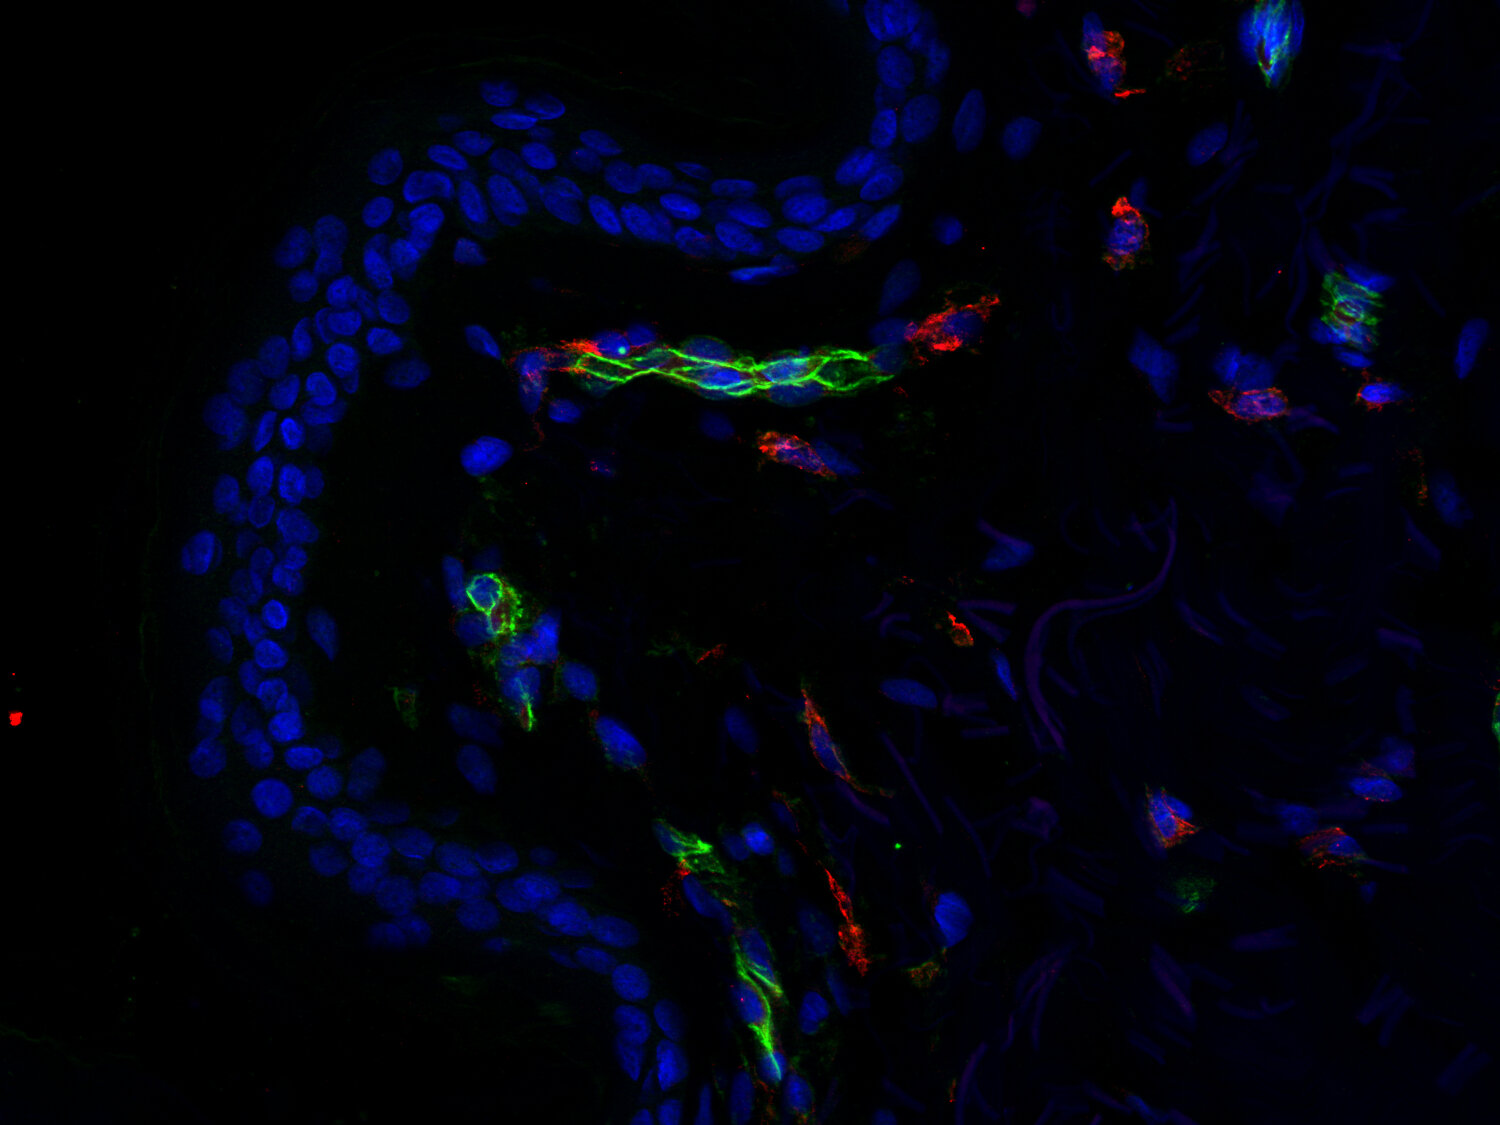

KRAS-dependent glycolytic reprogramming of endothelial cells in sporadic arteriovenous malformations.

Wu R, Khosraviani N, Mansur A, Boudreau E, Largoza GE, Park S, Gustafson D, Raju S, Ching C, Klip A, Wälchli T, et al.

EMBO molecular medicine (2026) : . HS-351 004 IHC; tested species: human